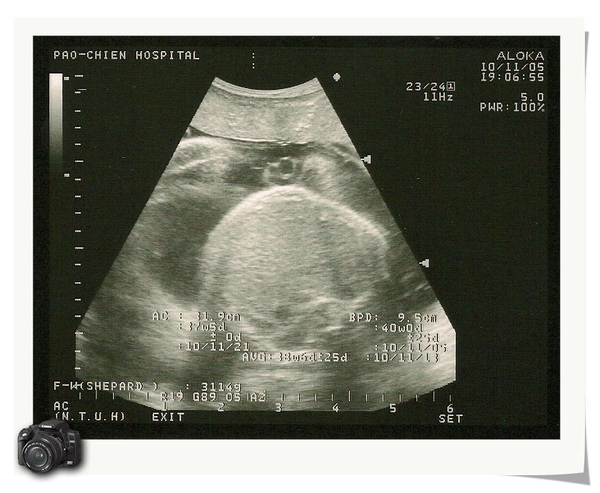

兩個星期一次的產檢又到囉!秤體重時,已經心裡有數,想說應該會超過70KG,果然.........剛剛好70KG,小寶弟照超音波,哇...........3100G耶!真是嚇到我了,醫生說如果我怕小朋友太大不好生的話,教我考慮38M的時候去醫院催生,可是我又很怕會像第一胎一樣,生一整天,想到就覺得好恐怖唷!!今天晚上要開始一週一次的產檢了,看看情況再說囉!!!

小寶弟的肚子醫生說這張超音波是小寶弟在吃手指頭,看的出來嗎??ㄎㄎleaf0817 發表在 痞客邦 留言(0) 人氣(24)